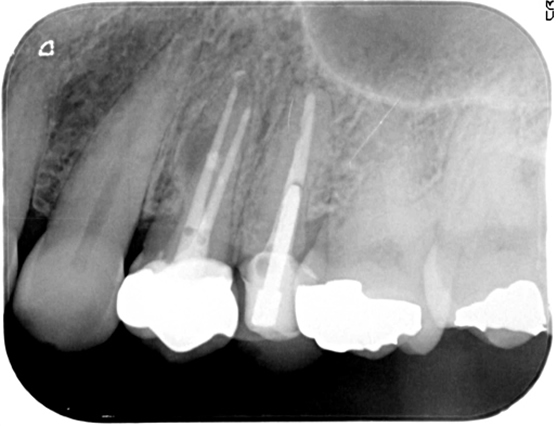

歯根端切除術

歯根端切除術は、歯根の先端の感染源を切り取り、薬を詰める治療法です。通常の根管治療だけでは治らない場合・何らかの理由で通常の根管治療が行えない場合に行います。